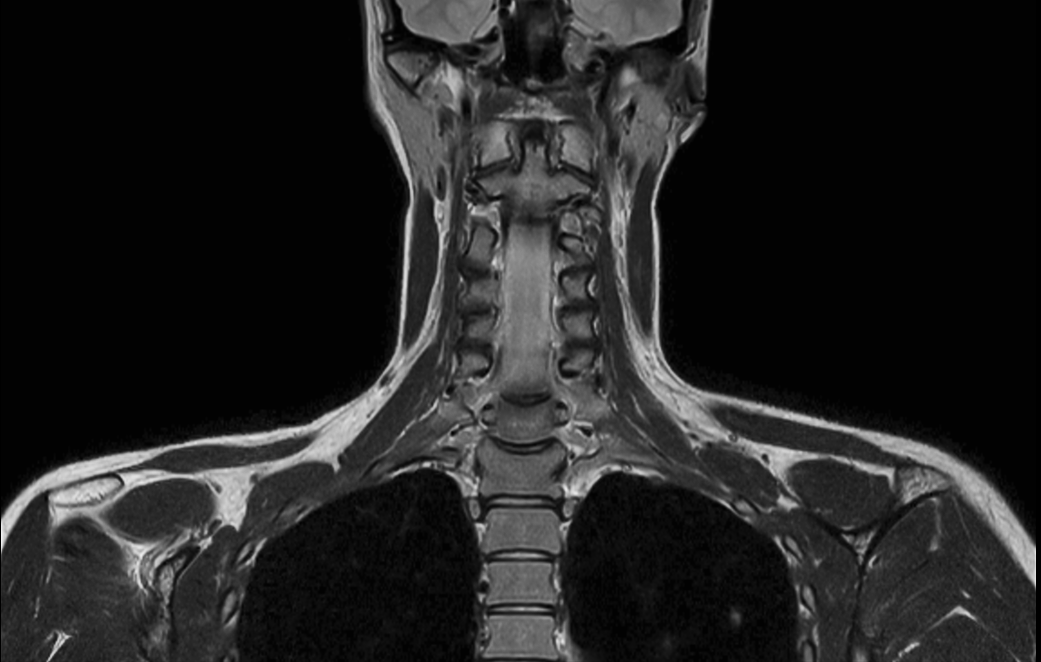

Coronal T2w  mDIXON TSE (In Phase)